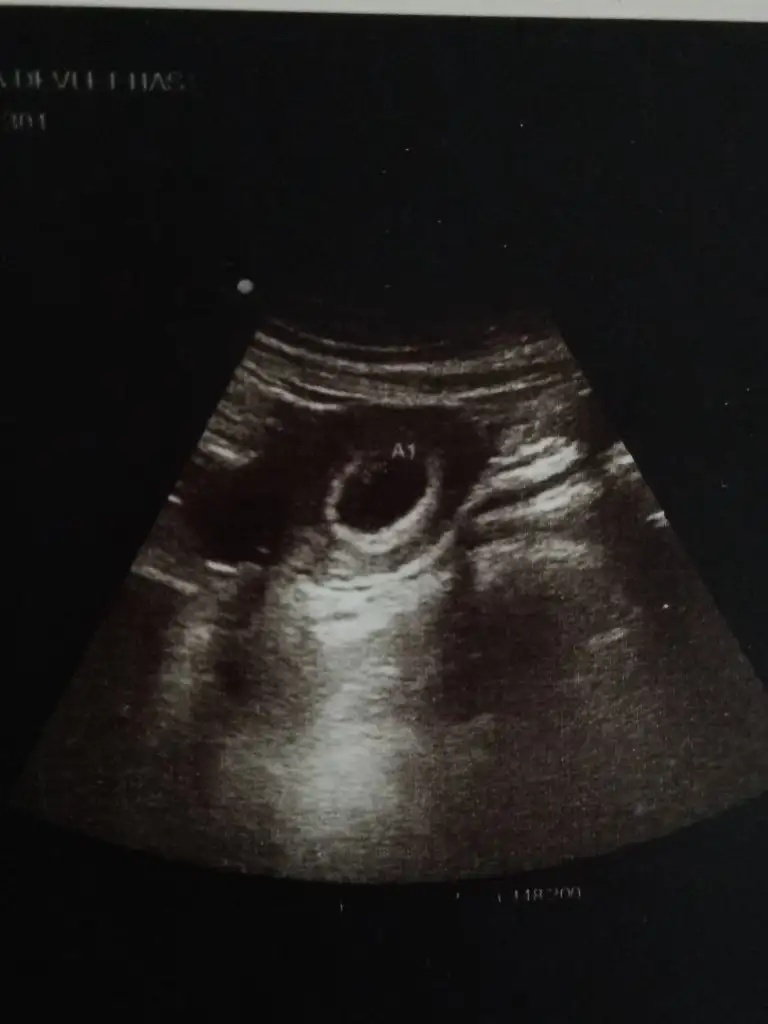

Yerm senin minnoşuda..kese şekillerimiz sennle aynı hemen hemen bende niye tam yuvarlak değil diyodm